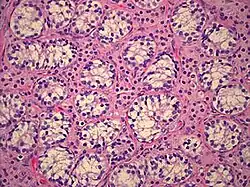

The gonads in people with CAIS are testes; during the embryonic stage of development, testes form in an androgen-independent process that occurs due to the influence of the SRY gene on the Y chromosome.[26][27] They may be located intra-abdominally, at the internal inguinal ring, or may herniate into the labia majora, often leading to the discovery of the condition.[1][28][29][30] Testes in those affected have been found to be atrophic upon gonadectomy.[31]

Immature sperm cells in the testes do not mature past an early stage, as sensitivity to androgens is required in order for spermatogenesis to complete.[32][33] Germ cell malignancy risk, once thought to be relatively high, is now thought to be approximately 2%.[34] Wolffian structures (the epididymides, vasa deferentia, and seminal vesicles) are typically absent, but will develop at least partially in approximately 30% of cases, depending on which mutation is causing the CAIS.[35] The prostate, like the external male genitalia, cannot masculinize in the absence of androgen receptor function, and thus remains in the female form.[18][36][37][38]

CAIS is also associated with an increased risk for gonadal tumors (e.g. germ cell malignancy) in adulthood if gonadectomy is not performed.[34][66][67][68] The risk of malignant germ cell tumors in women with CAIS increases with age and has been estimated to be 3.6% at 25 years and 33% at 50 years.[68] The incidence of gonadal tumors in childhood is thought to be relatively low; a recent review of the medical literature[66] found that only three cases of malignant germ cell tumors in prepubescent girls have been reported in association with CAIS in the last 100 years. Some have estimated the incidence of germ cell malignancy to be as low as 0.8% before puberty.[1]